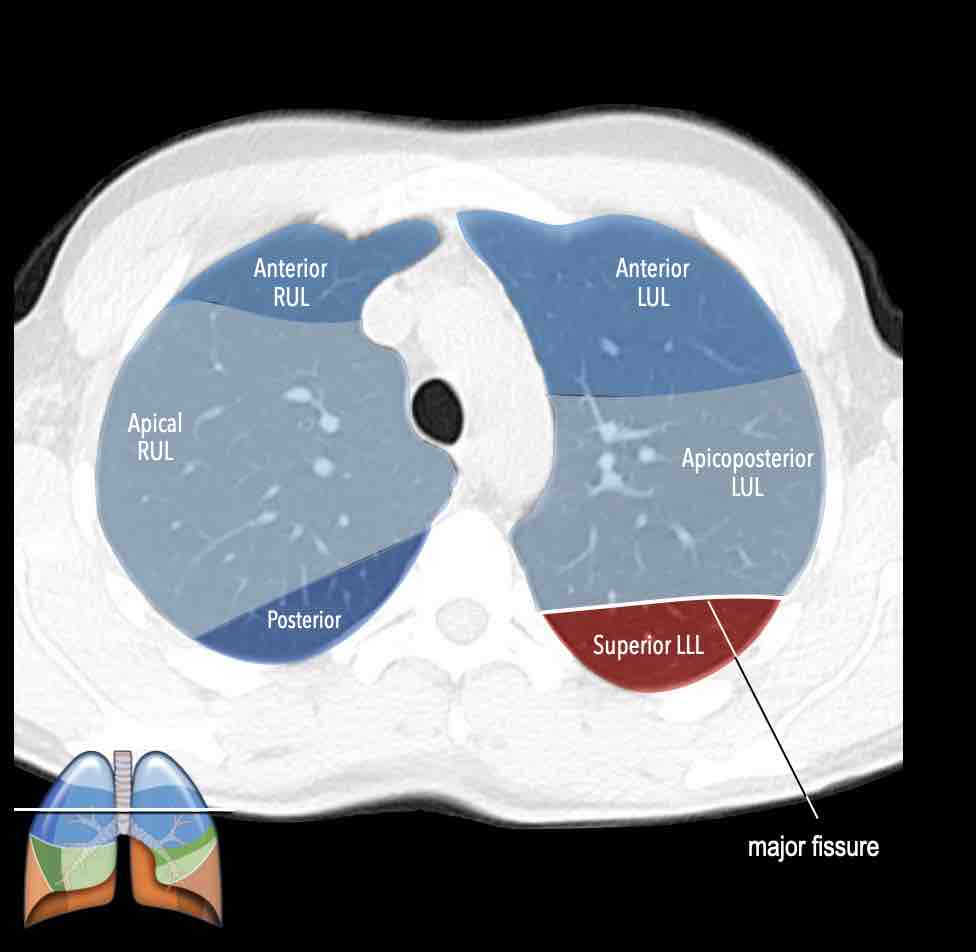

Các phân thùy phổi trên CT

Cuộn qua các hình ảnh để quan sát cách phổi được phân chia thành các phân thùy.